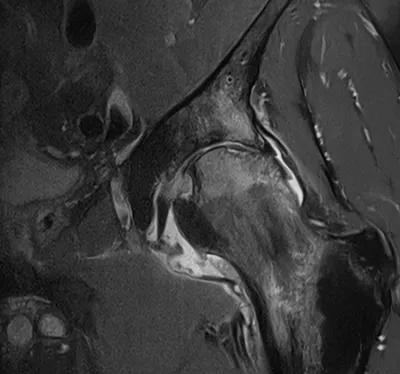

Ischiofemoral impingement

MRIPelvisAxial+1

4/23/2026